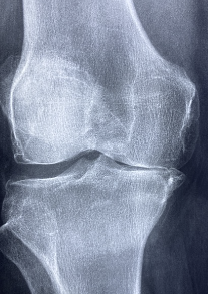

무릎 관절 통증 원인

무릎 관절 통증은 여러 가지 원인에 의해 발생할 수 있습니다. 대표적인 원인은 다음과 같습니다.

- 연골 손상: 연령이 들어가면서 무릎 관절의 연골이 마모되어 손상이 발생할 수 있습니다. 이는 일상적인 사용, 부상, 비만 등으로 인해 발생할 수 있습니다.

- 인대 손상: 무릎 관절 주변의 인대가 파열, 늘어남, 부분적으로 손상되어 통증을 유발합니다. 인대 손상은 스포츠나 사고 등으로 인해 발생할 수 있습니다.

- 퇴행성 관절염: 노화로 인해 무릎 관절의 연골이 마모되고, 인대 및 근육 등도 약화되어 통증을 유발하는 질환입니다.